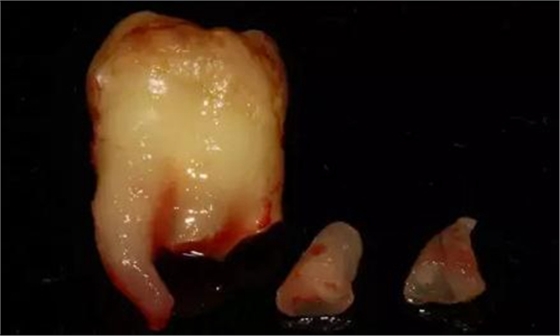

下面看一個(gè)病例,患者,女,30歲,因左下頜智齒嵌塞食物后疼痛,至當(dāng)?shù)匮揽平o予拔除,但術(shù)后1個(gè)半月,患者自覺(jué)拔牙區(qū)一直隱隱疼痛,時(shí)輕時(shí)重,遂來(lái)診。檢查發(fā)現(xiàn),拔牙創(chuàng)口一直未愈合,未見(jiàn)明顯腫脹,拍片發(fā)現(xiàn),拔牙窩內(nèi)顯示高密度斷根影

像,該斷根臨近下頜神經(jīng)管,同時(shí)發(fā)現(xiàn)第二磨牙遠(yuǎn)中有兩塊高密度影像,疑似殘留骨片或牙片,應(yīng)該是引起疼痛的原因,經(jīng)與患者溝通,采納建議,進(jìn)行二次拔牙。